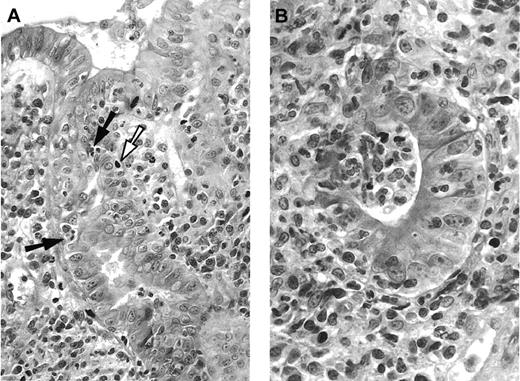

Histologic digestive GVHD (Figure 1) was found in 68 of 93 (73.1%) patients. Thirty-three (48.5%) patients had grade 1, 21 (30.8%) patients had grade 2, 11 (16.2%) patients had grade 3, and 3 (4.5%) patients had grade 4 histologic digestive GVHD.

(A) Duodenal biopsy with apoptotic epithelial cells (white arrow), some of them in close contact with intra-epithelial mononuclear cells (black arrows), and dense infiltrate in the lamina propria, composed mononuclear and polynuclear cells. Hematoxylin-eosin, × 250. (B) Higher magnification of damaged glandular epithelium “exploding crypt” in the lamina propria. Hematoxylin-eosin, × 400.

Before day 100, 15 of 16 (93.7%) patients with diarrhea of more than 500 mL per day had histologic digestive GVHD. This was also the case for 31 of 39 (79.4%) patients with diarrhea lower than 500 mL per day and for 7 of 13 (53.9%) patients with only nausea or vomiting (Table 2). After day 100, 15 of 25 (60%) patients had histologic digestive GVHD.